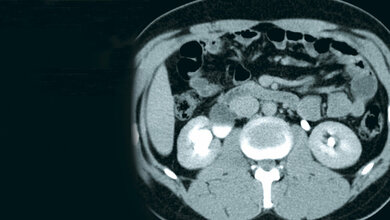

Der Fokus liegt auf den diagnostischen Ansätzen und unterschiedlichen Therapieformen von Harninkontinenz. Erarbeitet wurde die Leitlinie unter der Federführung der DGGG e. V. mit Beteiligung zahlreicher weiterer Fachgesellschaften. Die Empfehlungen beziehen sich auf die Therapie von erwachsenen Frauen im ambulanten sowie stationären Versorgungsbereich.

Die ausführliche und sorgfältige Anamnese – so betonen die AutorInnen – ist der erste und grundlegende Schritt bei der Behandlung. Auch die Untersuchungs- und Behandlungserwartungen sollten in diesem Zuge ermittelt werden. Je nach Art der Erkrankung – Belastungsinkontinenz, Mischharnkontinenz oder Dranginkontinenz – wird zwischen konservativer, medikamentöser und operativer Therapie unterschieden. Die konservative Therapie erstreckt sich auf einfache klinische Maßnahmen, lebensstilbezogene Interventionen, wie etwa Koffeinreduktion, körperliche Aktivität, Gewichtsreduktion, und individuelle Verhaltens- und Physiotherapie. Für die medikamentöse Therapie wird je nach Ausprägung der Harninkontinenz der Einsatz von entsprechenden Arzneimitteln empfohlen. Führen konservative und medikamentöse Maßnahmen nicht zum erwünschten Erfolg sieht die Leitlinie individuelle operative Therapien vor. Zuletzt widmen sich die AutorInnen der Diagnose und Behandlung von urogenitalen Fisteln, die eine Harninkontinenz herbeiführen können.